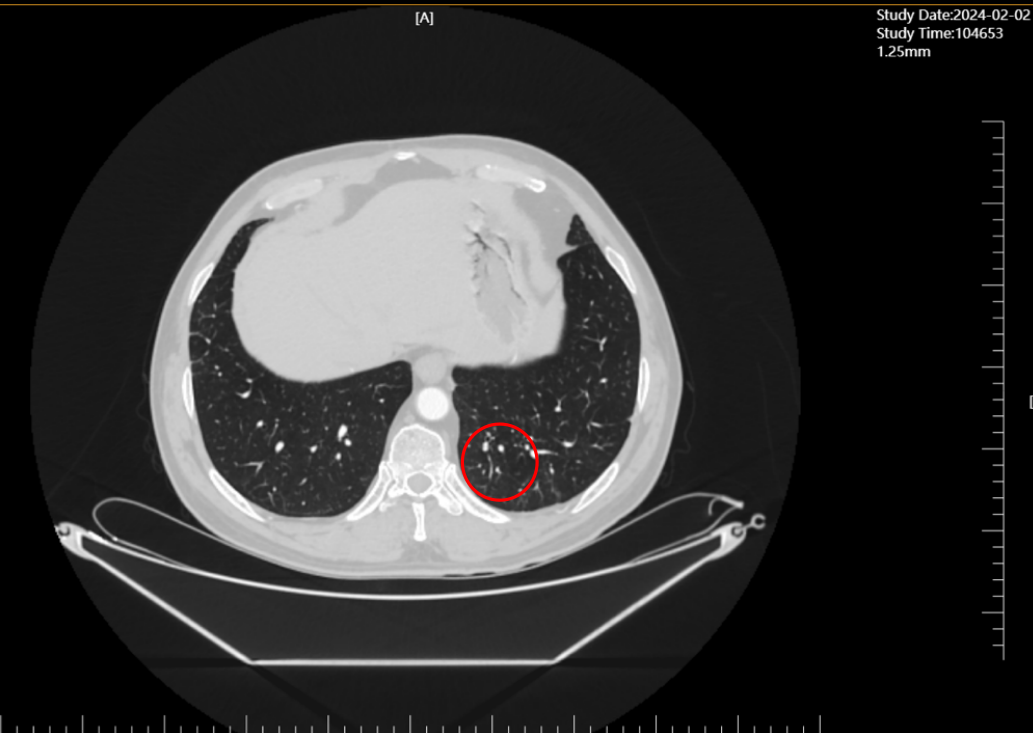

2024年2月(单药维持3个月),经影像科与肿瘤科联合评估,达到完全缓解(CR)——这是晚期肺癌治疗中的“技术里程碑”,意味着体内可检测肿瘤病灶完全消失。

截至2025年10月,肖先生已实现“从发病到无瘤生存2年5个月”,且停抗肿瘤治疗3个月后复查胸部CT,无任何肿瘤复发迹象——这一成果远超晚期肺鳞癌传统治疗的生存预期,背后是我院肿瘤科“技术驱动临床”的深刻实践: